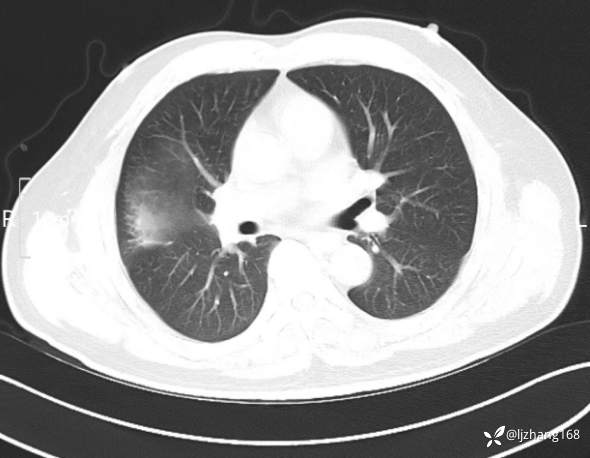

中年男患,右肺团片影,炎症0R肿瘤?

辅助检查:糖化血红蛋白12.3%。肺炎支原体IgG、IgM、呼吸道合胞病毒均未见明显异常。胸部CT:右肺上叶阻塞性肺炎。